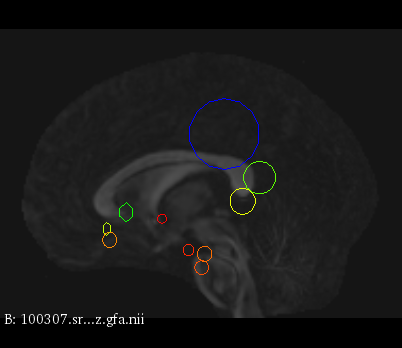

Figure 3 provides a scale-space visualization of feature matches for a single pair of MZ twins and NT siblings, where scale information is represented using the circle radius. Note that circles represent the intersection of 3D spheres with the visible slice and, thus, non-intersecting features are hidden in this 2D visualization.

It can be seen that different image modalities generally result in distinct, complementary feature correspondences throughout the brain, allowing a rich characterization of both anatomical and connectivity structure. In T1 and T2 images, features are mainly located in the frontal lobe, corpus callosum and brain stem. Smaller-scale features are also visible along various cortical regions, as well as in sub-cortical structures near the basal ganglia. Although highly correlated, T1 images show significantly more feature matches than T2 images. Moreover, images based on diffusion measures have less matches than in structural modalities. These matches are located mostly inside or near to white matter: larger-scale features in the corpus-callosum, and smaller-scale ones in the brain stem and along white matter bundles. While not shown in the figure, the set of matches found by combining two modalities (e.g., T1 + T2) generally corresponds to the union of those obtained with these individual modalities.

Comparing different sibling types, we observe a greater number of matches between MZ twins than NT siblings. This observation, which is easier to visualize in T2 and GFA images, is consistent with other analyses on twin datasets. In terms of feature location and scale, no obvious pattern can be seen when comparing these two sibling types. However, a more detailed analysis would be required to validate this assertion.